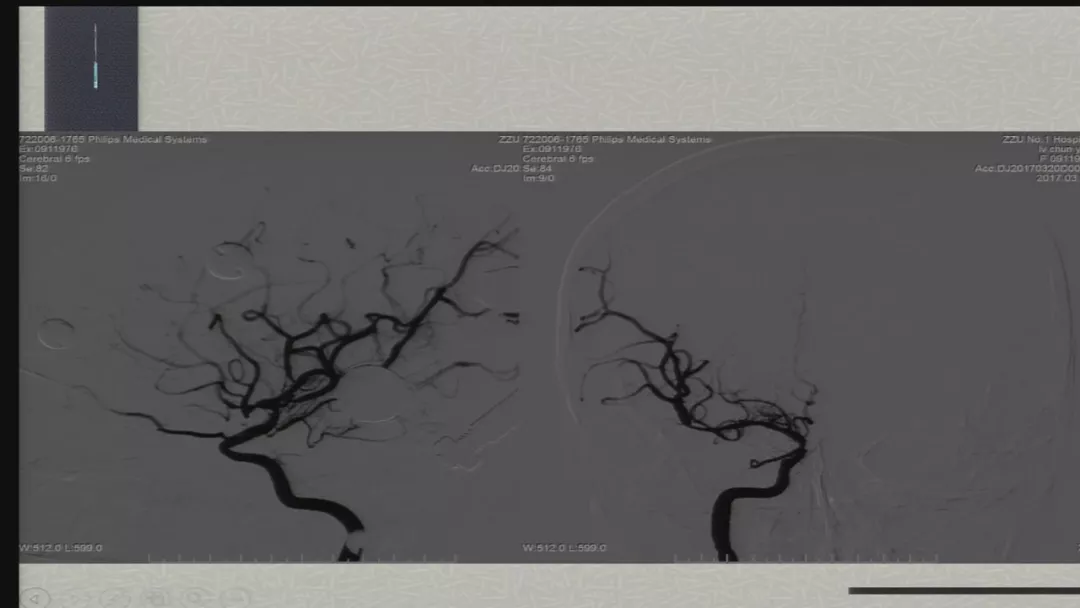

今天为大家分享的是由郑大一附院徐浩文教授在第七届全国介入医学工程大会上带来的“Neuroform EZ在ICAD治疗中的应用”精彩讲课视频和PPT,欢迎观看!(内容未经讲者审核,不当之处请与我们联系)